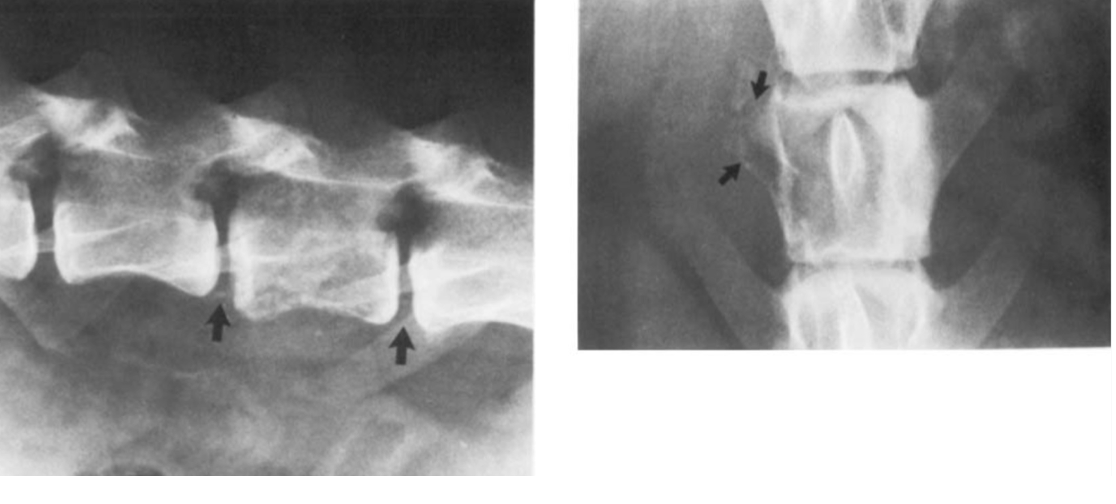

You have a yorkie presenting with hindlimb ataxia. there is pain involved and an acute onset. you take rads and see this. what is happening? how do you treat it?

A

atlantoaxial subluxation

young toy breed:

any age/breed: trauma

neck pain > ataxia > weakness > paralysis

tx: conservative (rest, neck brace, pain meds), sx

px is good for young dog, acute onset with mild C/S